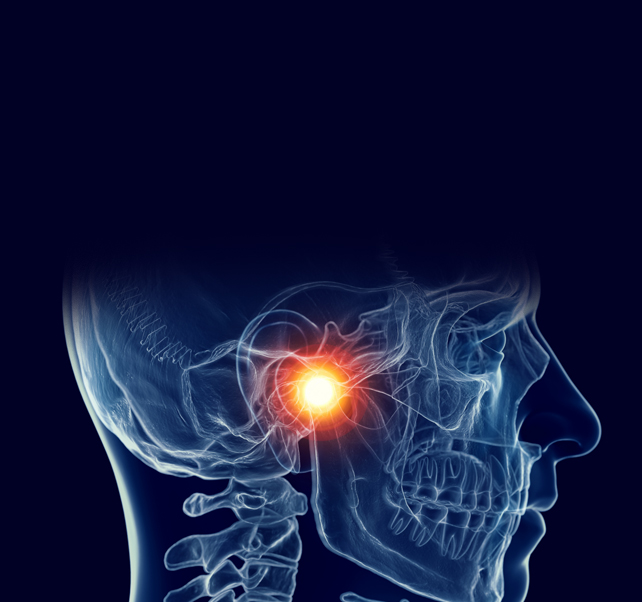

ㆍ턱관절 교육연수회 Course 수료

ㆍ대한턱관절교합학회 회원

ㆍ 턱관절 교육연수회 Course 수료

ㆍ 대한턱관절교합학회 회원